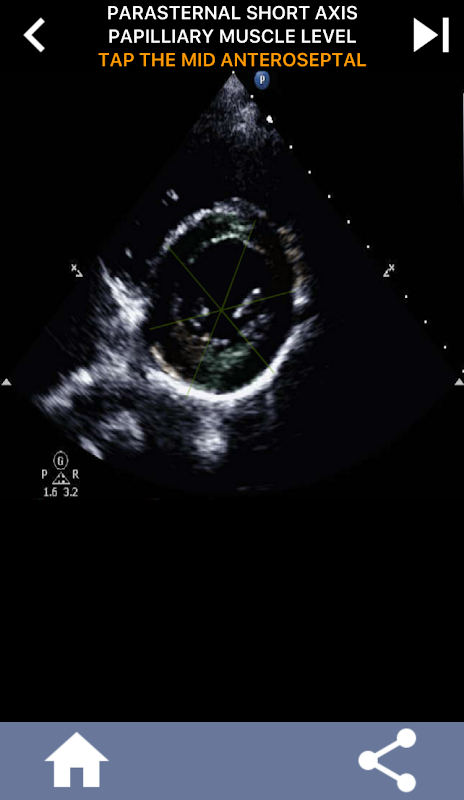

Abordagem visual baseada em questionário para aprender os segmentos cardíacos da AHA: ecocardiografia

Esse entendimento torna-se particularmente crucial quando o cardiologista procura determinar a localização precisa de um problema ou quando o médico de plantão identifica um problema em uma região específica, levando o ultrassonografista a exibir com precisão o segmento correspondente, como a parede médio-inferior. Assim, possuir uma compreensão abrangente dos segmentos cardíacos da AHA é um conjunto de habilidades essenciais.

Este aplicativo testará seu conhecimento usando imagens de eco reais, que geralmente considero o melhor método de ensino.